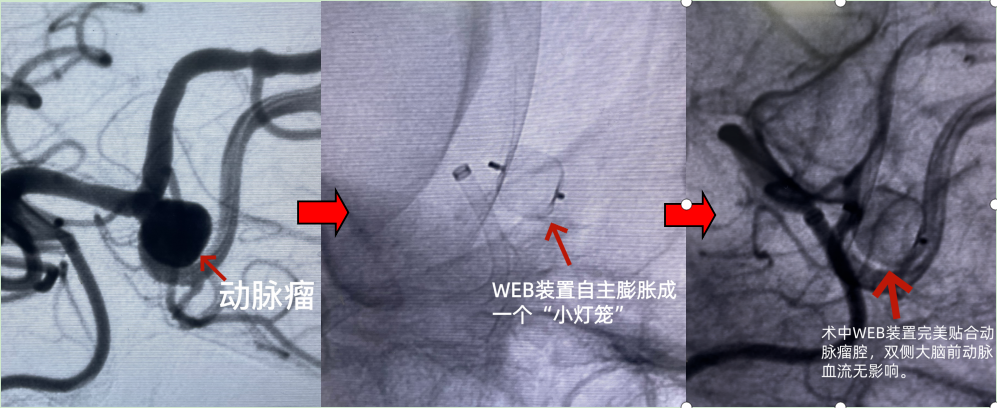

术中,手术团队经股动脉穿刺,将压缩的WEB装置通过微导管精准输送至动脉瘤腔,装置自主膨胀成网状球体——“小灯笼”并完美贴合瘤壁。经造影确认双侧大脑前动脉血流无影响,观察15分钟后完成装置解脱。手术精准高效,术后复查显示,WEB装置完全填塞动脉瘤腔,载瘤血管通畅,患者未出现任何神经系统并发症,3天便顺利出院。

患者手术过程